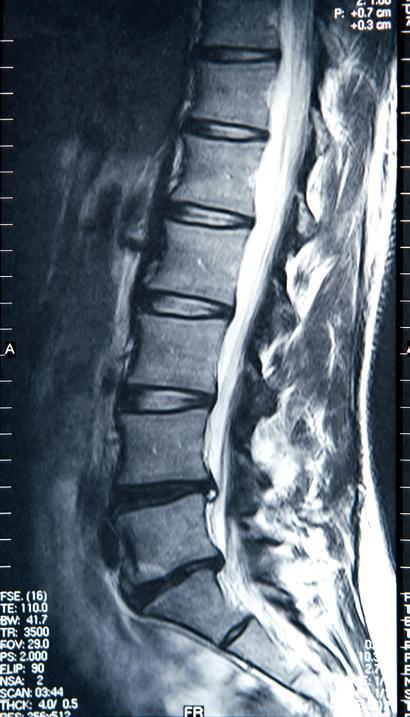

MRI

Magnetic resonance imaging (MRI) is a non-invasive study that uses magnetic energy and radio waves, not radiation, to produce a detailed two- or three-dimensional image of structures inside the body. MRI scans map the location of water and fat in the body and produce detailed spatial images. MRI is a useful tool for diagnosing and monitoring myeloma because of its ability to image early focal lesions in the bone marrow. Because MRI creates images of soft tissue, it can show small clumps of myeloma in the bone marrow, plasmacytomas, and compression of the spinal cord by these masses.

The best setting for MRI is early in diagnosis. MRI is highly sensitive for the detection of focal lesions before bone destruction occurs. In a large comparative study of X-ray and MRI, 52% of patients had normal-appearing

whole-body X-ray but had focal lesions that were apparent on MRI. The IMWG guidelines on MRI state that because MRI is a more sensitive study than X-ray for focal lesions (before the appearance of lytic bone lesions), all SMM patients should undergo whole-body MRI (WBMRI) or spine and pelvic MRI if WBMRI is unavailable.

The limitations of MRI include the following:

¡ MRI is an expensive, timeconsuming procedure.

¡ Patients who have metal implants, and patients who are claustrophobic, cannot undergo MRI.

13. Example of an MRI study

¡ There is a lag time of about 9 months or longer before an MRI will look normal after an area of myeloma has been successfully treated. Because this leads to a high falsepositive rate, the IMWG guidelines state that the use of MRI “for the follow-up of patients, before or after different therapies, in the absence of clinical indications is not recommended.”

¡ Treatment for myeloma will interfere with MRI results. If possible, myeloma patients should not start treatment before a scheduled MRI.

¡ The MRI scanning technique that is best for myeloma (with diffusionweighted imaging) has not been standardized and is not widely available.